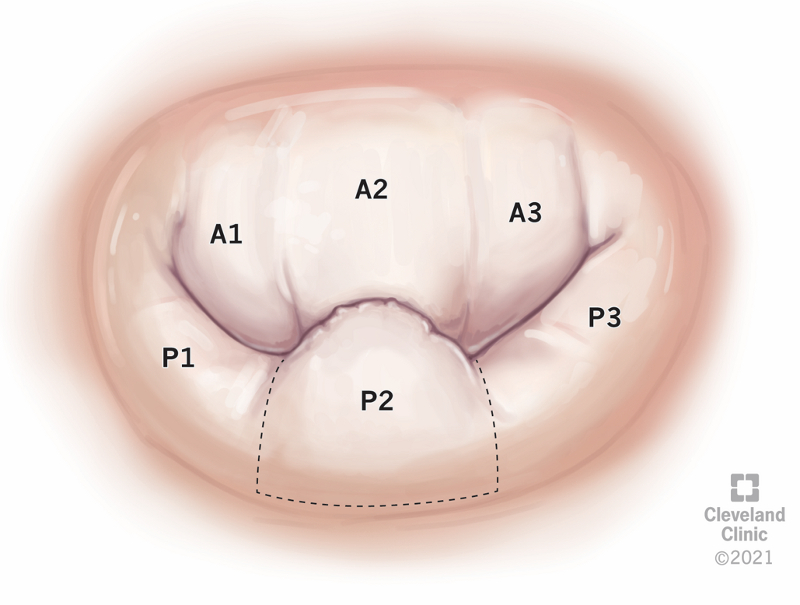

Prolapso da valva mitral

vista "en-face" da valva mitral com prolapso único do segmento P2

Reimpresso com permissão, Cleveland Clinic Center for Medical Art & Photography ©2021. Todos os direitos reservados